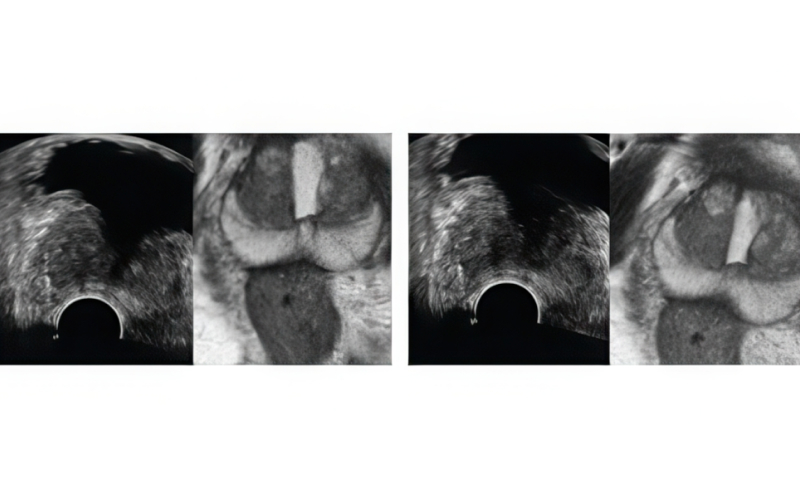

기존 검사는 병변 유무와 관계없이 12군데를 무작위로 채취해 정확도가 낮고 재검 가능성이 높았습니다. 하지만 MR 퓨전 조직검사는 병변을 직접 겨냥해 조직을 채취하므로 진단율이 크게 향상되었습니다.

최첨단 AI와 3D 융합 영상으로 진단 정확도를 혁신적으로 높인 골드만만의 특별한 조직검사입니다.